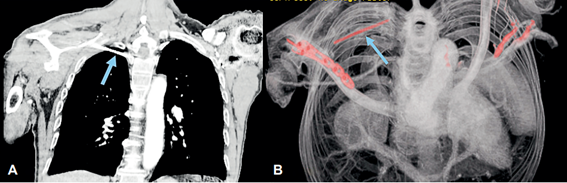

Un mes después consultó por presentar dolor severo en hombro derecho y dificultad respiratoria de dos días de evolución. En la radiografía de hombro derecho se observó migración de uno de los clavos de Kirschner, ubicado en el aspecto superior del hemitórax ipsilateral (Figura 3). Se solicitó una angiotomografía de tórax que evidenció un cuerpo extraño ubicado en la región infraclavicular, que correspondía al clavo de Kirschner intratorácico, y el extremo distal en contacto con el parénquima pulmonar del segmento apical del lóbulo superior derecho. No presentaba neumotórax, focos neumónicos ni lesión vascular (Figura 4). Los laboratorios no mostraron leucocitosis, ni neutrofilía, por lo cual no requirió antibioticoterapia.

La planificación del abordaje para la extracción del clavo debe hacerse sobre la tomografía, para conocer exactamente la localización de este dentro del tórax 12,21. En el caso informado, mediante tomografía se identificó la ubicación intratorácica del clavo de Kirschner, y por lo tanto se decidió realizar la toracoscopia 16,21. Antes se habían descrito abordajes como la toracotomía y esternotomía 22,23para la extracción de los dispositivos o los cuerpos extraños alojados en el tórax, bien sea en la pleura o el pericardio, pero ahora el procedimiento de elección es la toracoscopia 21,24-26, por tener múltiples ventajas sobre la cirugía abierta.